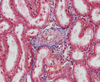

renal corpuscle (or glomerulus)

visceral layer (podocytes), glomerular (Bowman’s) capsule

parietal layer, glomerular (Bowman’s) capsule

glomerular urinary space

endothelial cells

podocytes

mesangial cells

up urinary pole of renal corpuscle

vp vascular pole of renal corpuscle

md macula densa

vascular pole and macula densa

extraglomerular mesangial cells = extraglomerular mesangium

juxtaglomerular cells

juxtaglomerular cells